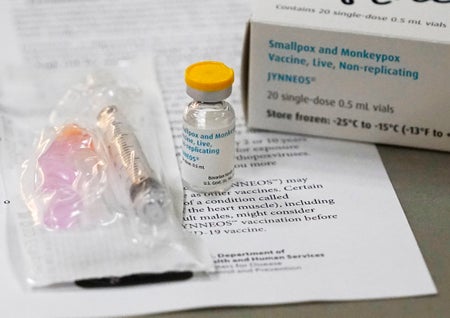

6 Questions about Monkeypox Vaccines

A virologist explains how they work, who can get them and how well they prevent infection

There Is an Effective Treatment for Monkeypox, but It’s Hard to Get

A smallpox antiviral that’s effective against monkeypox is tied up in red tape, and gay-health advocates are pushing to make it easier to access

The antiviral Tecovirimat (TPOXX) shows promise against monkeypox, but human data and supplies are limited

The antiviral Tecovirimat (TPOXX) shows promise against monkeypox, but human data and supplies are limited